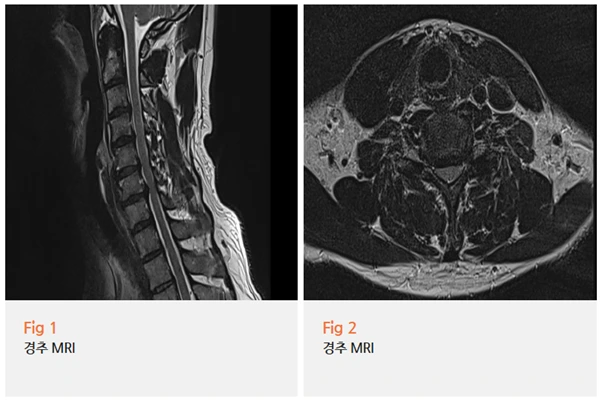

하지만 당일 MRI를 포함한 여러 검사를 진행한 결과...

예상대로였습니다.

경추 4-5번, 5-6번, 6-7번에서 추간판 탈출증이 확인됐고,

경추 협착증 소견도 함께 있었어요.

그리고 신경전도 및 근전도 검사에서는

좌측 경추 6번 신경근병증이 급성으로 악화된 상태였습니다.